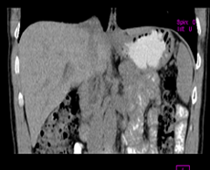

患者,男,57,常年不吃午饭,近一个月来腹部隐痛,无明显黄疸,明天进行增强扫描,图象另上传,麻烦各位帮忙一起看看讨论讨论

肝外胆管扩张,胰头增大,肠系膜上静脉似有包埋征象。

考虑:胰头占位性病变,建议增强进一步检查。

肝外胆管扩张,胰头增大,占位性病变可能性大.

肝外胆管稍扩张,胰腺钩突略增大,但外形尚可,境界清楚。(常年不吃午饭)提示胰腺炎可能大,肿瘤第二步考虑。

支持考胰头占位性病变,感觉十二指肠壁不规则增厚,不排除十二指肠降部占位可炎症

胰头增大,考虑胰头占位性病变。

胰头增大,胆总管增宽,考虑胰头癌可能性大,明天看增强片有助诊断.